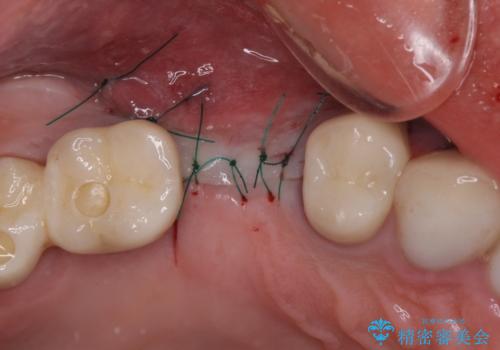

- 咬合力により歯が割れてしまった方のインプラント治療です。

抜歯後4ヶ月ほど待ち、後方のインプラントと同一メーカーのインプラントを埋入することとしました。

大変怖がりであるため、インプラント治療の際には静脈内鎮静により、眠っている間に手術を行いました。

別途費用はかかりますが、術中の記憶はほとんどなく、処置もあっという間に終わった感覚となるので、大変お勧めです。